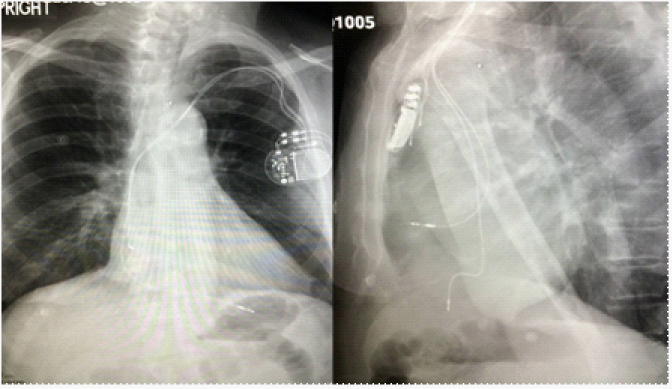

Post-operative chest X-Ray confirmed correct lead placement. However the ECG was done which showed a RBBB morphology with mean QRS of -86degrees (Figure 2). Repeat PA and lateral chest x-ray next day (Figure 3) and a 2D echocardiogram (2D ECHO) (Figure 4) were done to confirm the lead placement as well to r/o any inadvertent position of the lead. All modalities confirmed RV apical lead placement and uncomplicated RV pacing. Following Pacemaker implantation, patient’s breathlessness and fatigability were markedly improved. He was regularly followed in the clinic initially after 3months and then every 6months. He continues to be in an improved state of health.

Figure 3 PA and lateral Chest X ray showing normal position of lead.